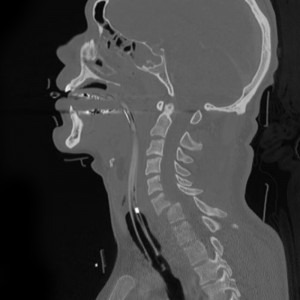

The term “whiplash” does not define just one condition but rather describes a variety of neck injuries that often occur in rear-end collisions. This term applies particularly to damage that occurs to the soft tissue of the neck. What happens in a rear-end car accident is the impact of the crash causes both the driver and the passengers to lunge forward while their heads remain in place. This causes the neck to suffer an unnatural extension and bending that results in a whip-like motion. These types of injuries are usually referred to as whiplash.

There are a couple of misconceptions about whiplash that are important to know. The first one is these types of injuries are not limited to high speed, serious accidents. In fact, it is quite common for whiplash to occur during rear-end collisions at low-speeds. Another misconception is that whiplash is not a very serious injury because it only involves soft tissue. However, contrary to this belief, medical evidence supports the premise that soft tissue injuries can be just as serious as other injuries, and if they are not treated can have long-term effects.